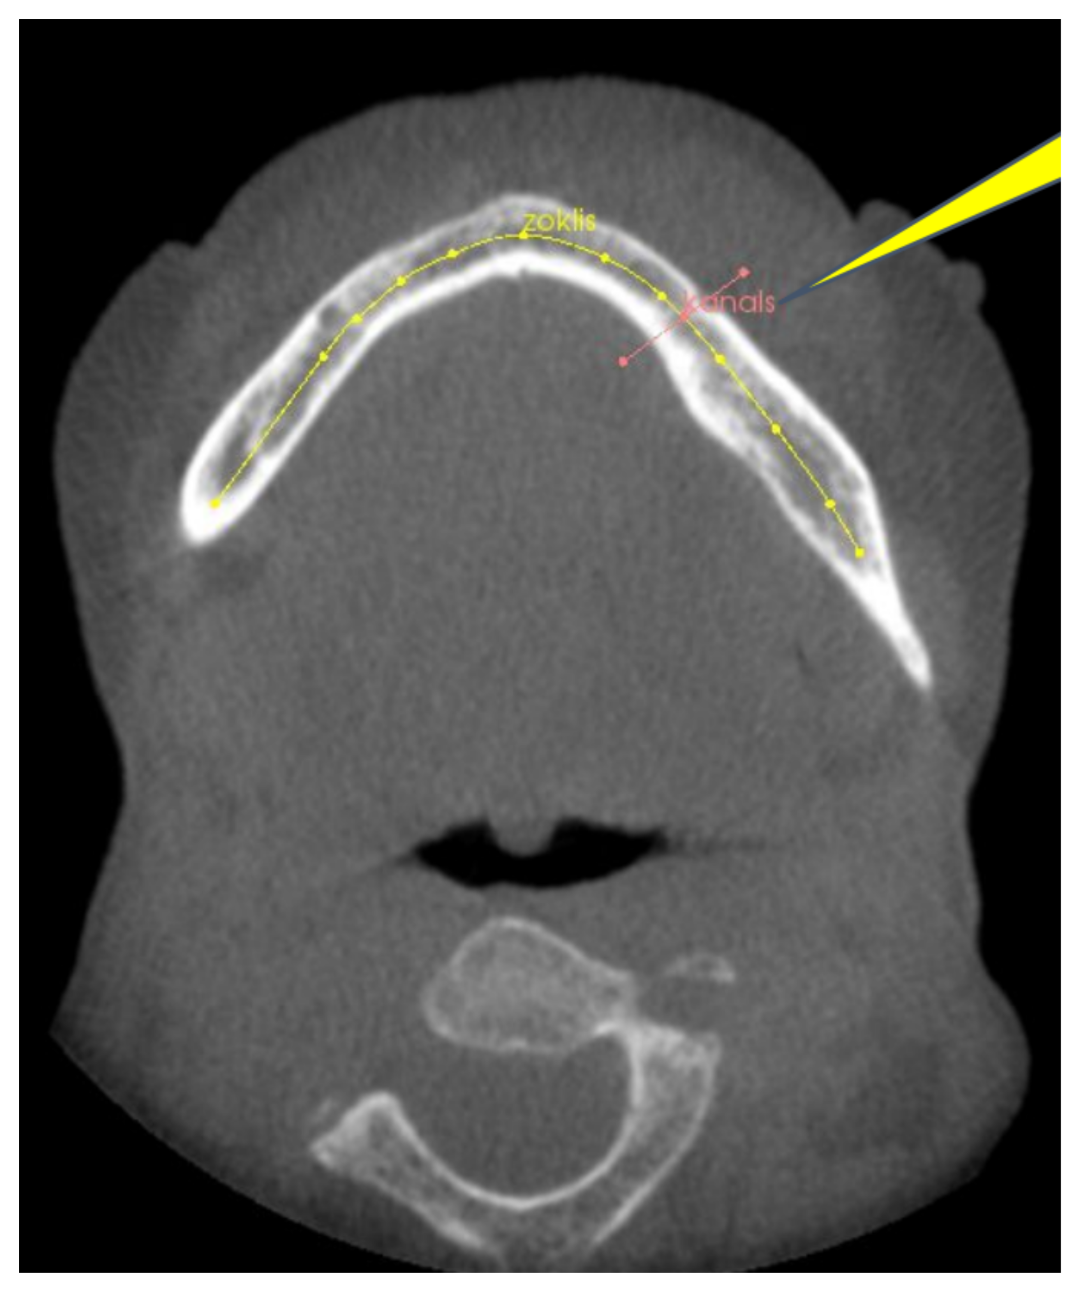

- Edgars Edelmers, Dzintra Kazoka, Katrina Bolocko, Kaspars Sudars, Mara Pilmane, Automatization of CT Annotation: Combining AI Efficiency with Expert Precision

- Ivars Namatevs, Arturs Nikulins, Edgars Edelmers, Laura Neimane, Anda Slaidina, Oskars Radzins, Kaspars Sudars, "Modular Neural Networks for Osteoporosis Detection in Mandibular Cone-Beam Computed Tomography Scans",

- Kaspars Sudars, Ivars Namatevs, Arturs Nikulins, Edgars Edelmers, Laura Neimane, Anda Slaidina, Oskars Radzins, "Artificial Intelligence-Powered System for Identifying Bone Deterioration in Radiological Imaging", International Workshop on Embedded Digital Intelligence (IWoEDI'2023)

- Ivars Namatevs, Kaspars Sudars, Arturs Nikulins, Anda Slaidina, Laura Neimane, Oskars Radzins, Edgars Edelmers, "Denoising Diffusion Algorithm for Single Image Inplaine Super-Resolution in CBCT Scans of the Mandible", 023 IEEE 64th International Scientific Conference on Information Technology and Management Science of Riga Technical University (ITMS)